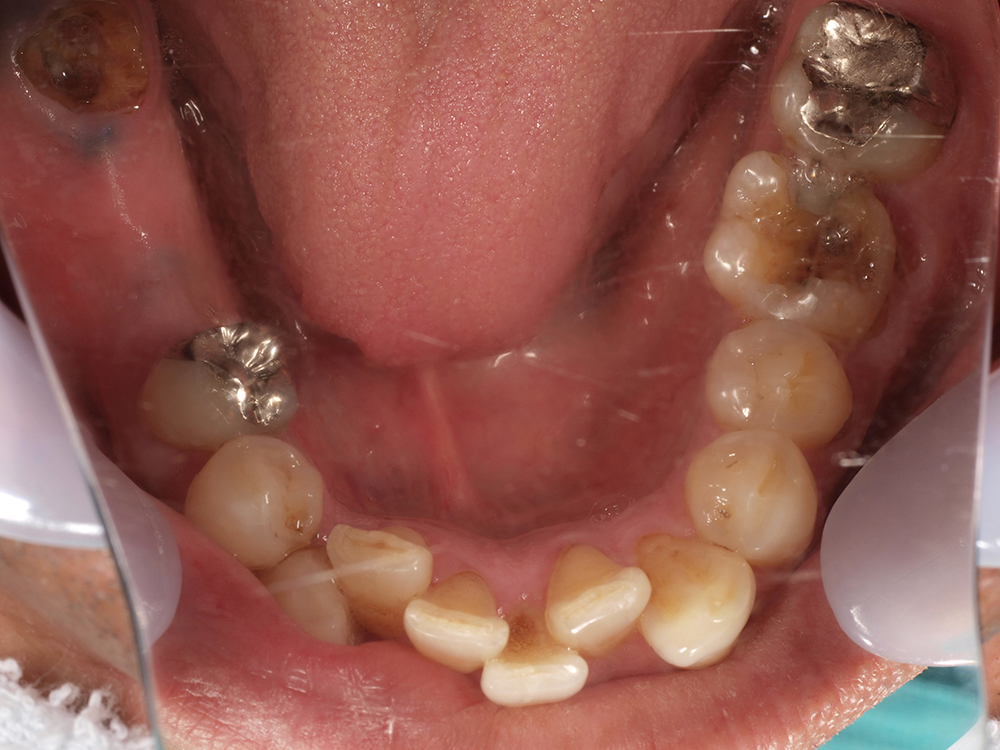

55歳 男性

- 主訴

- 前歯でしか咬めなく、食事を採るのに非常に困難で辛い

- 処置内容

- 上顎6本、下顎3本

- 治療費用

- 上顎:約230万(税込)下顎:約120万(税込)

- 治療期間

- 上顎:1年(仮歯まで8か月)下顎:8か月(仮歯まで5か月)

- リスク

- 上部構造物、仮歯の破折、術後の腫れ(3日)、人工歯根脱落リスクがあります